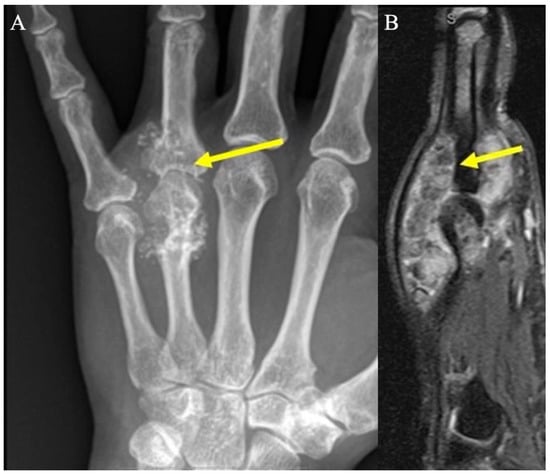

2.8. Synovial Chondromatosis

2.8.2. Imaging Appearance